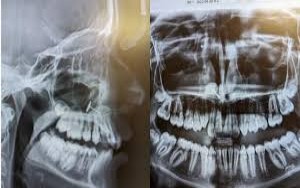

बेटी के दांत का एक्स-रे देख मां, समेत डॉक्टर भी चौंके, फिर खुल गया राज...

वॉशिंगटन,। अमेरिका के वॉशिंगटन स्टेट में महिला अपनी बेटी को साधारण डेंटल चेकअप विजिट के लिए ले गई, लेकिन…